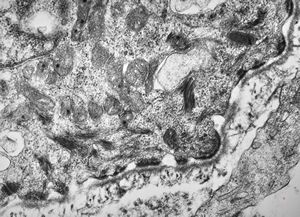

normal seromucinous salivary gland